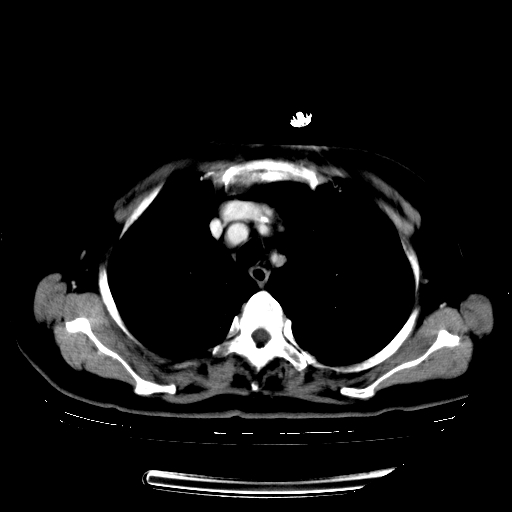

标题: CT23067:女,70岁,咳嗽、咳痰一个月,低热一周。 [打印本页]

女,70岁,咳嗽、咳痰一个月,低热一周。

1、右肺占位,考虑周围型ca 。

2、右下肺软组织密度肿块影,考虑肺隔离征。

3、两肺肺结核(右肺下叶背段及左肺)。

4、主动脉夹层。

5、右侧少量胸腔积液。